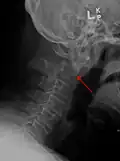

Type 3 odontoid fracture -

Type 2 dens fracture